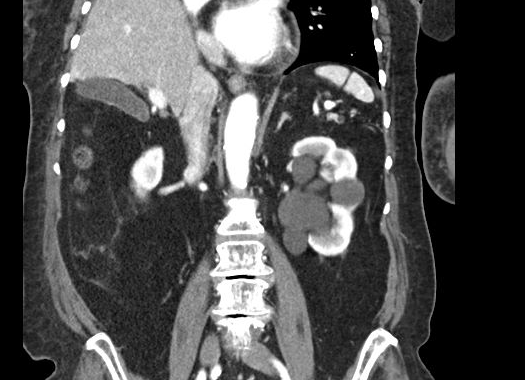

Our patient had a multicystic lesion in the head of the pancreas suggestive of a serous cystic neoplasm.  She also had multiple cystic pancreatic tail lesions thought to represent intraductal papillary neoplasms.  In addition, she had a renal sinus cyst on the left which can mimic hydronephrosis.